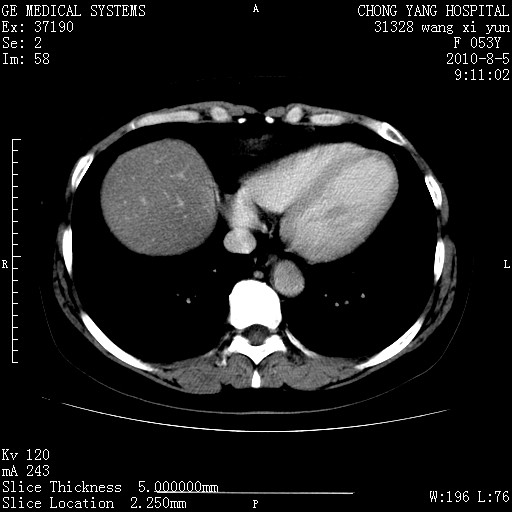

标题: CT28214:F41Y 血尿二十天,建议盆腔平扫加增强。

胆管细胞ca?

1)考虑肝左叶胆管细胞癌。2)脂肪肝。

支持胆管细胞ca。